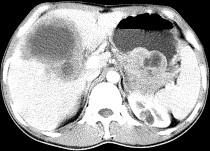

问题 女,61岁,上腹部疼痛一个月,食欲减退,消瘦,CT所见如图,最可能的诊断是 ( )

选项 A.肝脓肿 B.肝转移瘤 C.胃癌肝转移 D.肝包虫病 E.原发性肝癌

答案 C